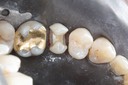

Scott Kanamori #31 finish buccal